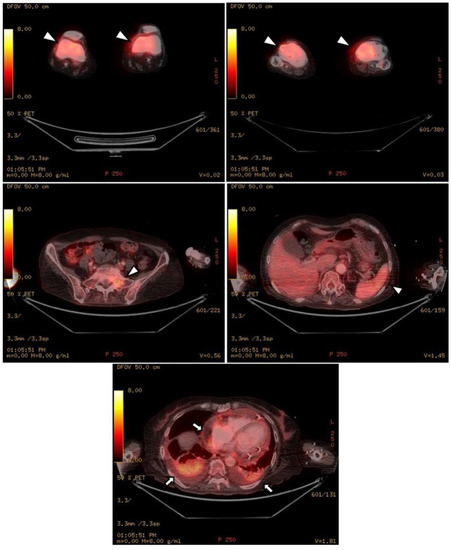

Figure 4.

Upon PET-CT, there is diffuse FDG uptake in both distal femurs, proximal tibia, sacrum, and spleen, which shows increased metabolic activity (white arrowheads). As shown in the chest and abdominal CT, there is pericardial effusion and pleural effusion shown by FDG uptake in the pericardium and pleura (black arrows).